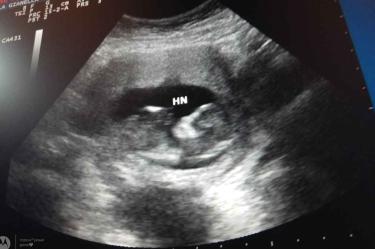

El doctor Sosa Olavarría, señaló que, en el área materno-fetal, el uso el ultrasonido es indispensable, ya que gracias al ultrasonido obstétrico se obtienen imágenes del embrión que está dentro de una mujer en gestación; esa información, precisó, “será de suma utilidad para el proceso del embarazo, desde etapas muy tempranas se puede identificar malformaciones congénitas.

“Desde etapas muy tempranas, en un embarazo entre la 4.ª y 5.ª semanas, se puede seguir la evolución del embrión a lo largo de la vida; establecer sus parámetros de crecimiento y desarrollo desde el punto de biometría, establecer su peso, talla y diagnosticar, además, las alteraciones del crecimiento y desarrollo”.